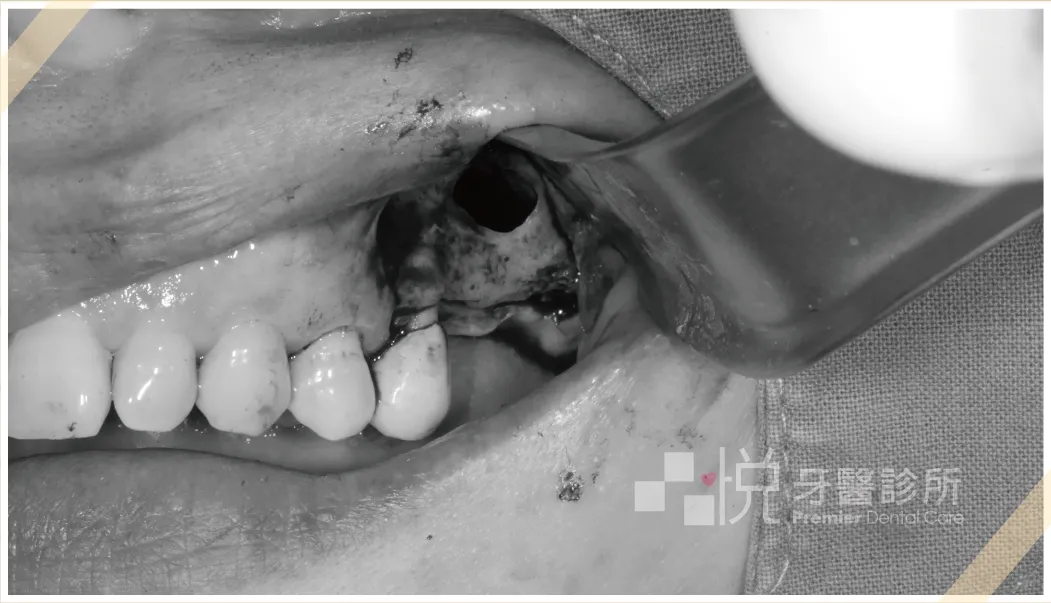

➋ 於要鼻竇增高之處形成骨窗,先把鼻竇膜露出。

➌ 使用器械把鼻竇膜往上剝離,並向騰出來的空間填塞骨粉